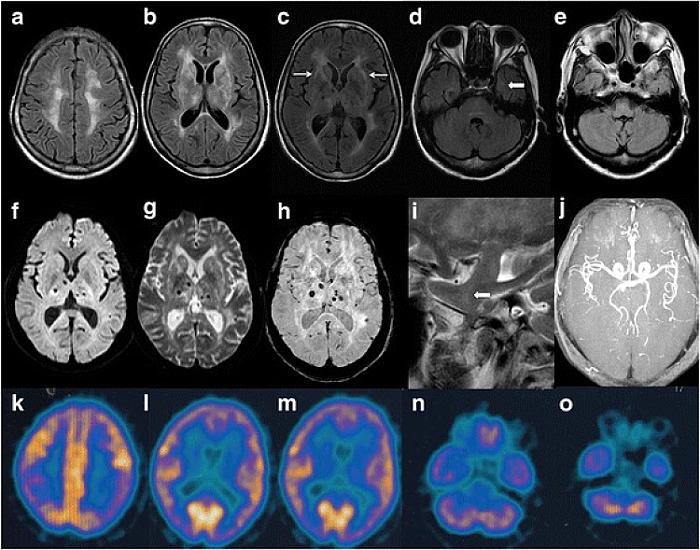

Mütəxəssislərin sözlərinə görə, bu patologiya adi yuxusuzluqdan fərqlənir. Xəstələr ümumiyyətlə yata bilmir, nəticədə beyin sürətlə zədələnir və funksiyalarını itirir.

Nevroloq Selia Qarsiya Malo bildirib ki, xəstəlik talamusun fəaliyyətinin pozulması ilə əlaqədardır və əsasən 30-60 yaş arasında başlayır. Bir neçə ay ərzində isə ölümə gətirib çıxarır.

Xəstəliyin əlamətlərinə yaddaş problemləri, hərəkət pozuntuları, əzələ seğirmələri və hallüsinasiyalar daxildir. Hazırda bu xəstəliyin effektiv müalicəsi mövcud deyil.